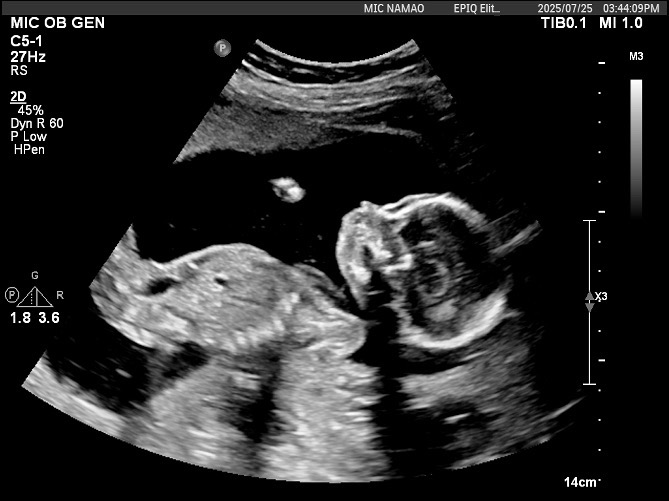

19주 초음파 사진으로 성별 알수있을가용

아직 성별을 모르는데 받은 사진이 이거뿐이라 ㅜㅠ 이 사진으론 알기 쉽지않겠죠?

19주는 각도법 볼 수 없어요... 그리고 위 사진 생식기도 안보이구요.

축하합니다 딸이네요